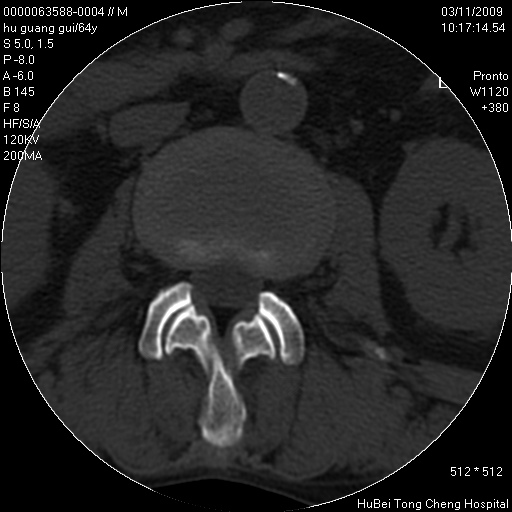

患者 男,64岁。腰痛十余天。(临床未提供其他病史)

临床诊断:腰痛原因待查(腰椎间盘突出症?)。

腰椎间盘ct轴位平扫(层厚5mm,层距4mm),图像如下:

腰椎退行性变,腰4—5椎间盘膨出。

右侧骶骨侧块骨侵蚀,骶髂关节骨性关节面破坏,并见软组织肿块,考虑骨转移瘤可能,进一步检查。

1.腰椎退行性变,腰4—5椎间盘膨出。

2.右侧骶骨侧块骨侵蚀,骶髂关节骨性关节面破坏,并见软组织肿块,考虑:脊索瘤,骨转移瘤可能,进一步检查。

1)腰椎退行性变,l4—5椎间盘膨出。2)骶骨右侧块骨转移瘤可能,3)水平骶椎。建议作一步检查。